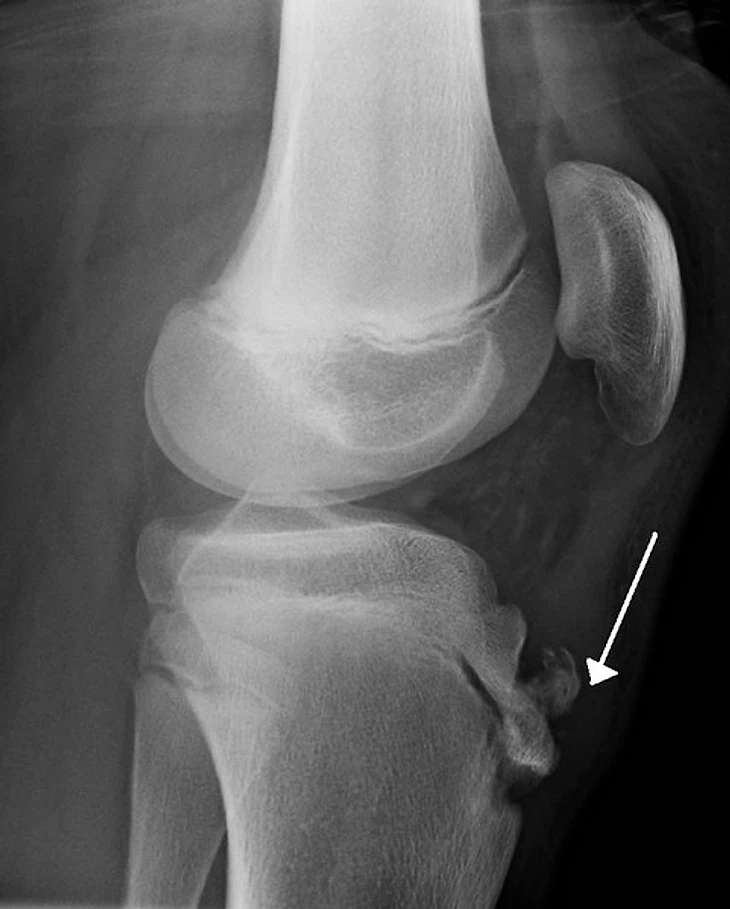

Несмотря на то, что Сеан обладал невероятной техникой и владением мяча в академии от него больше требовали физики, и здесь у худощавого парнишки не задалось. Спустя некоторое время его тело не справилось с недетскими нагрузками и у него начала проявляться болезнь Осгуда-Шляттера. Это достаточно редкая травма в футболе, но очень серьезная и зачастую ставит карьеру под угрозу. Коленный состав Гарнье увеличился, а колено опухло до таких размеров, что больше напоминало бедро. Но тренерам «Осера» было плевать на состояние здоровья юноши, как вспоминал позже Гарнье: «Наставнику было достаточно того, что я мог ходить, а если ты можешь ходить значит можешь и тренироваться». После тренировок Сеан уходил в себя и плакал, игра которая раньше дарила исключительно положительные эмоции превратилась в адскую боль и страдания, и если бы он так продолжил, то вполне мог стать инвалидом. Поэтому Гарнье решил взять перерыв чтобы залечить травму и вернутся уже более сильным и крепким.